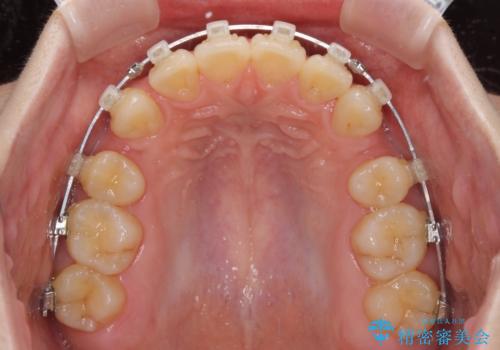

- クリアブラケット

- 3年10ヶ月

- 30回以上

深い咬み合わせは上顎前歯を引っ込ませる大きな障害となるため、咬み合わせの改善が非常に重要となります。やや期間はかかりましたが、当初狙った通りの仕上がりで治療を終えることができました。